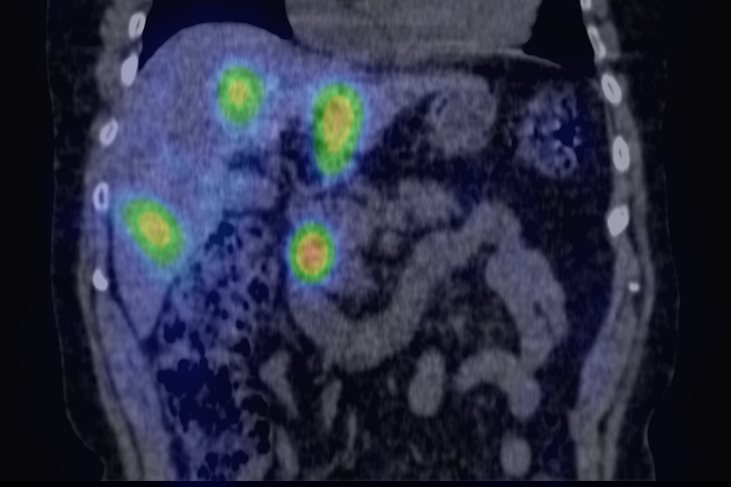

The greatest precision of image registration is achievable if the patient experiences minimal motion differences (the patient lies in the same position and imaging takes place almost at the same time) during both examinations. These requirements are met in hybrid imaging methods, with the implementation of the so called hardware registration. PET-CT, SPECT-CT or the newly emerging PET-MR examinations are all able to utilize hardware registration. The integrated PET/SPECT-CT method represents the latest technical developments of both PET and CT scanners, combined in one machine. It is capable to represent structural and metabolic information simultaneously and identically. The machine’s PET/SPECT and CT components are aligned along the common axial axis, and as the patient table moves along their longitudinal axis, the two examinations are carried out only minutes apart from each other, minimizing any movement or change in the patient’s position. During evaluation the identical slices of CT and PET can be matched with each other and they can be analyzed independently or represented in a fusion image. (Figure 1.)

1. Fusion images; FDG PET-CT, transversal and coronal planes. The dominance of certain components (transparency) can be constantly adjusted on the fused image.